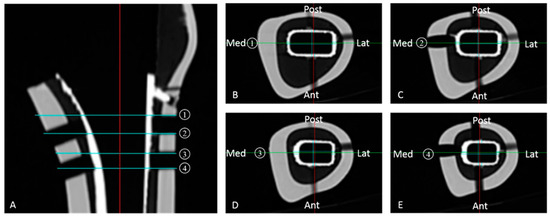

After the loading tests were completed, all stems were removed from the cement. CT images were then taken with a slice spacing of 1 mm to measure the thickness of the cement mantle. The average thickness of the cement was calculated using four scans of horizontal sections aligned with the insertion holes of the proximal rods. The thickness of the cement layer was measured in the middle of each of the anterior, posterior, medial, and lateral areas (Figure 4).

Figure 4.

CT images, taken after stem removal. CT images were taken at 1 mm slice spacing in four horizontal sections aligned with the insertion holes of the proximal lateral femoral rods to measure the cement thickness. (A) Coronal slice of femoral canal center. 1: Upper edge of proximal lateral hole for rod. 2: Lower edge of proximal lateral hole for rod. 3: Upper edge of distal lateral hole for rod. 4: Lower edge of distal lateral hole for rod. (B) Axial slice at the level of 1; (C) Axial slice at the level of 2; (D) Axial slice at the level of 3; (E) Axial slice at the level of 4. The thickness of the cement layer was measured at the midpoint of each area.